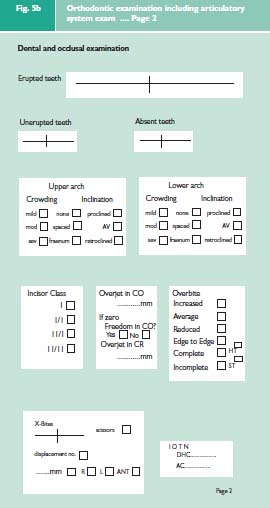

It is important to emphasise that it is necessary to carry out a full occlusal examination for all orthodontic patients. It is essential to record not only the patient’s habitual bite (centric occlusion CO or intercuspation position ICP) but also to record the patient’s ideal jaw relationship (centric relation = CR or retruded contact position = RCP). This is done against the benchmark of ‘ideal occlusion’.1 Firstly does CO occur in CR? If not, what is the discrepancy between the two? Secondly does the anterior guidance on the front teeth occur with an absence of posterior interferences?

The three elements of an examination of the articulator system2 can easily be incorporated into an orthodontic examination protocol (Fig. 5a–c). This comprehensive examination is divided into two main parts. The jaw and facial examination will record the pattern of the skeletal bases and the facial symmetry, the condition of the TMJs and mandibular muscles, and the soft tissue characteristics. The dental and occlusal examination will record the position of the teeth and their occlusal contacts.